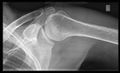

أشعة إكس

-

CR. shoulay film.

Transaxillary conventional radiography

Y-projection conventional radiography